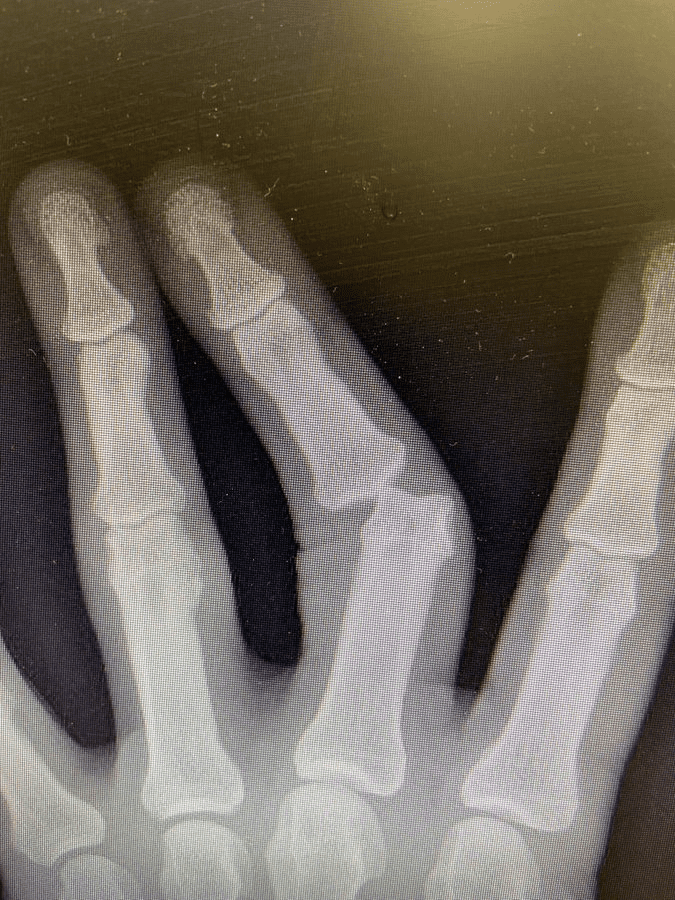

Dijak took to Twitter to give his fans a new look into his injury. His latest tweet shows an X-Ray photo of his hand where his middle finger is dislocated at the second joint. He didn’t include any caption, because one was not needed.

You can check out the X-Ray photo below. It remains to be seen how Dijak will come back from this injury. For more updates, stay tuned to Ringside News.